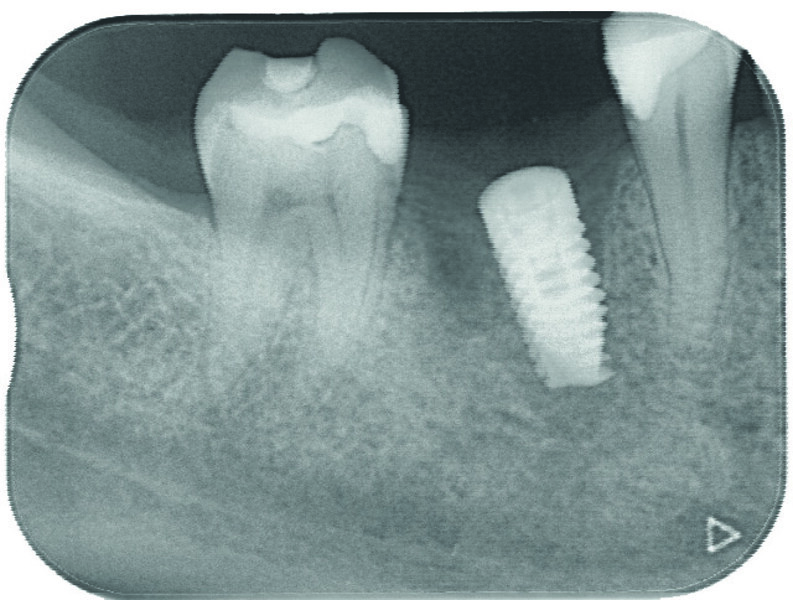

À l’issue de l’intervention, vérification de la correspondance entre la planification et la chirurgie avec une rétroalvéolaire (Figs. 11 et 12).

Fig. 12 : Radiographie de contrôle postopératoire de l’implant en 46.